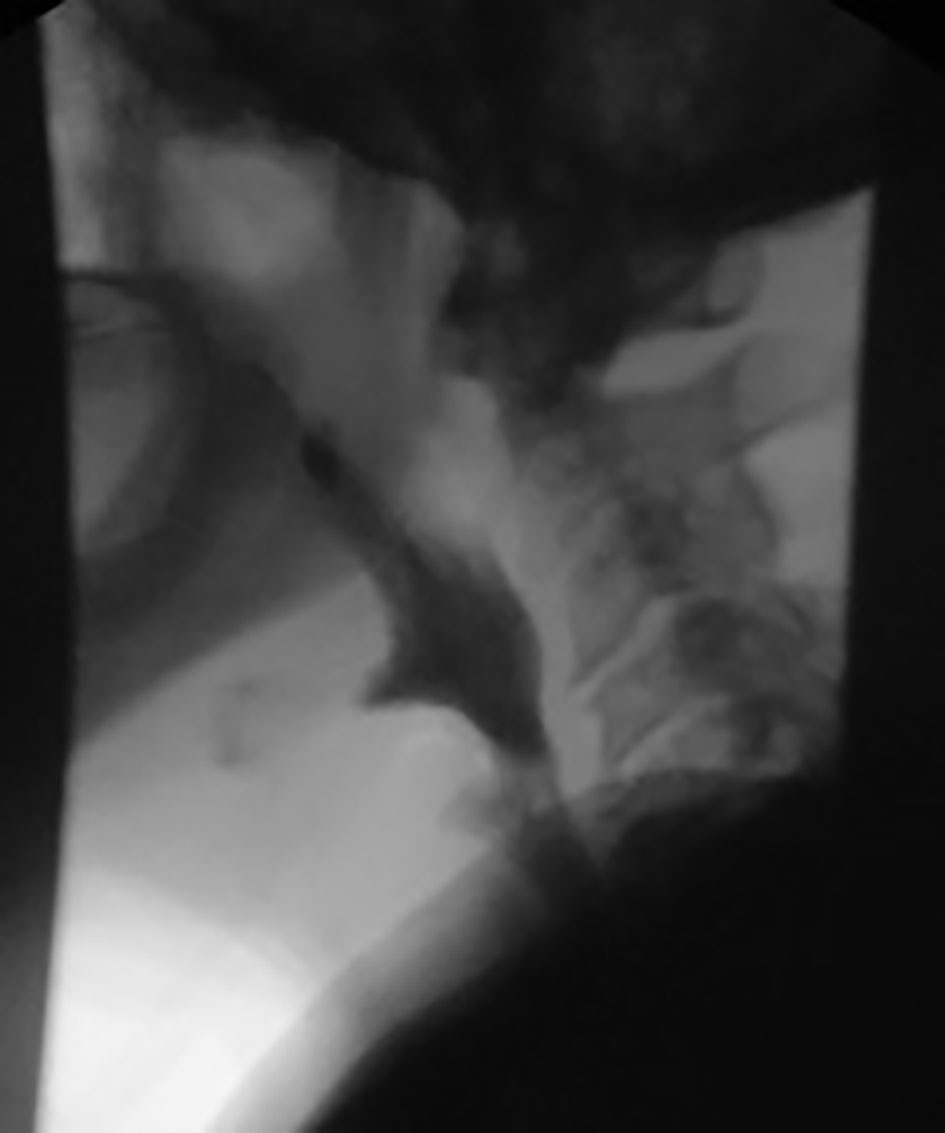

A 72-year-old male with past medical history of stage IV squamous lung cancer was brought to the hospital with complaints of anorexia, shortness of breath, and increased hemoptysis for preceding 4 weeks. His lung cancer was diagnosed 8 years earlier, when he presented with T4N2M0 non-small cell lung cancer treated with combined modality therapy consisting of chemotherapy and radiation to a dose of 6,480 cGy in 180 cGy fractions which led to a 7-year progression-free interval. One year earlier, he had recurrence of the cancer. Patient was not candidate for further radiation therapy. He received palliative chemotherapy with gemcitabine and carboplatin and after four cycles was placed on a chemotherapy holiday. Patient condition had been stable till 1 month prior to current admission when he developed progressive hemoptysis, right-sided chest pain and fatigue. On admission, chest X-ray (CXR) showed new worsened reticular markings along left lung base suggestive of infectious process. CT of chest showed findings consistent with interval progression of malignancy with an area of consolidation along the medial right lower lung (Fig. 1). Sputum culture showed mixed bacterial growth. Patient received short course of antibiotics followed by 10 fraction course of palliative radiation therapy. Immediately after completing his eighth cycle of radiotherapy, he developed progressive coughing and difficulty swallowing, together with shortness of breath, fever and confusion. He was readmitted, and CXR showed increased interstitial prominence at the bilateral lung bases. Laboratory workup revealed signs of infection with a WBC of 21.2 × 109/L. Procalcitonin was 0.12 ng/mL. He was diagnosed with hospital acquired pneumonia and received broad antibiotics coverage. His sputum culture revealed poly-microbial growth without organism identified. Due to concern of progressive coughing and difficulty swallowing a video, swallow evaluation was done. Surprisingly, it showed a TEF (Fig. 2) in the middle third of the esophagus. Patient underwent upper endoscopy and palliative esophageal stent placement (Fig. 3). Following successful stent placement, patient tolerated diet without complications. One week later, he was sent to hospice for further comfort measures.

![]() Click for large image | Figure 2. Video swallow evaluation shows a linear exclusion of contrast from mid esophagus into the tracheobronchial tree consistent with tracheobronchial fistula. |